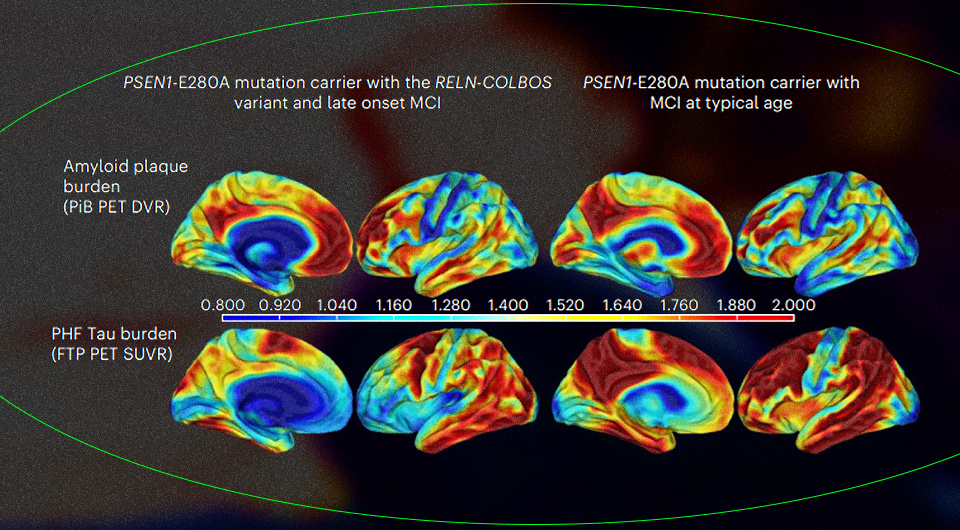

Еще один пациент с генетической предрасположенностью к болезни Альцгеймера сохранял рассудок почти до 70 лет. В 2019 году ученые описали случай женщины, которую от семейной болезни Альцгеймера защитила генетическая мутация. Теперь та же команда исследователей из Германии, Колумбии и США обнаружила мужчину, который, несмотря на генетическую предрасположенность к раннему развитию слабоумия, долгое время был когнитивно здоров. За его устойчивость к деменции отвечала уже другая мутация. Об этом ученые рассказали в Nature Medicine.

Иногда болезнь Альцгеймера может быть наследственной: к такой приводит мутация E280A в гене PSEN1, который кодирует мембранный белок пресенелин. Человеку достаточно получить одну копию такого гена от одного из родителей, чтобы эффект проявился. Когнитивное снижение начинается у таких пациентов довольно рано — примерно в 44 года, к 49 годам развивается слабоумие, а к 60 они умирают от осложнений.

В 2019 году Джозеф Арболеда-Веласкес (Joseph Arboleda-Velasquez) из Гарвардской медицинской школы и его коллеги из разных стран описали случай женщины, которая, имея эту мутацию, оставалась в полном здравии до 70 лет, и только потом встретилась с когнитивным снижением. Исследователи обнаружили у нее незначительные патологии мозга, но не смогли понять, когда они возникли — до развития когнитивных нарушений или после. Выяснилось, что у нее была мутация